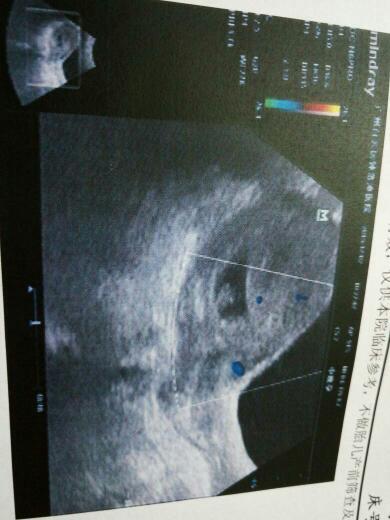

谁可以帮我看看这个彩超图是否怀双胞胎? 点击展开 匿名用户 2015-12-19 17:39 满意回答 你好,从超声报告单上看,只有纪恨一个孕囊和胎芽,不是双胎妊娠。祝刺指脚好孕。菠查 充听露_1Xbu 2015-12-19 17:41 宝宝知道提示您:回答为网友贡献,仅供参考。 相关问题 怀双胞胎27周了四维彩超还能做吗 怀双胞胎做不了唐氏筛查吗?现在四个半月了 四维彩超也做不了吗 怀双胞胎做不了唐氏筛查吗?现在四个半月了 四维彩超也做不了吗